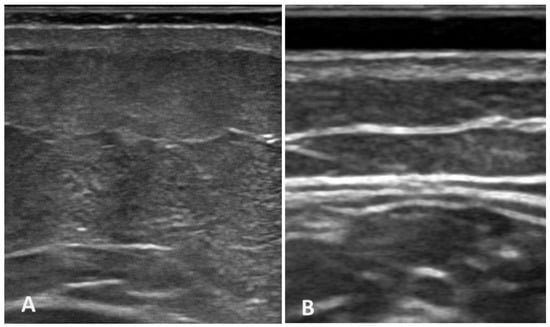

2.4. Ultrasound Image Analysis